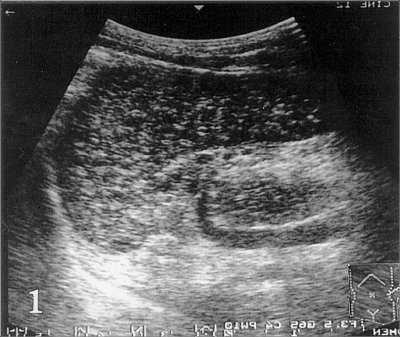

Рис. 1. На эхограмме селезенки больного циррозом печени и портальной гипертензией определяются мелкие диффузные гиперэхогенные включения (точечные кальцификаты).

Ответ: Тельца Гамна-Гэнди (Gamna-Gandy) в селезенке больного циррозом печени с портальной гипертензией.

На эхограмме в левой косой проекции (рис. 1) визуализируются диффузные гиперэхогенные включения (точечные кальцификаты) в селезенке, состоящие из телец Гамна-Гэнди. При сканировании в правом подреберье (рис 2b) визиализируется печень повышенной эхогенности, с неоднородной структурой, образованием узлов в ее паранхиме и расширением пупочной вены.

Тельца Гамна-Гэнди представляют собой ограниченные организованные кровоизлияния в селезенке, вызванные портальной гипертензией. Тельца Гамна-Гэнди состоят из фиброзной ткани, гемосидерина и кальция.

Они обычно расположены в перифолликулярной и трабекулярной зоне и состоят из фиброзной ткани, с вкраплениями гемосидерина и кальция. Yasuhara с соавторами при проведении УЗ-исследования определяли тельца Гамна-Гэнди в виде диффузных гиперэхогенных включений, подобные повреждения они обнаружили на аутопсии у 12,9% больных циррозом печени. Изучив корреляцию морфологических и эхографических признаков, авторы пришли к выводу, что эхография позволяет увидеть в селезенке тельца Гамна-Гэнди диаметром больше 1 мм и широко распространенные. Тельца Гамна-Гэнди определяются при портальной гипертензии, синдроме Банти, наследственном сфероцитозе, застойной сердечной недостаточности, внутрибрюшинном воспалении или при прорастании воротной вены карциномой желудка либо карциномой поджелудочной железы. Тяжелые хронические заболевания и их осложнения могут вызывать образование расссеянных кальцифицированных очагов. Наиболее частой причиной является туберкулез. Рассеянные кальцификаты возникают также при длительно текущем гистоплазмозе или токсоплазмозе. При цистицеркозе они обнаруживаются значительно реже. Длительно существующая застойная селезенка вызывает значительное увеличение органа. Селезенка становится плотной, и плотность ее увеличивается по мере нарастания застойных явлении. Капсула селезенки становится утолщенной и фиброзированной, но не вовлекается в процесс. На срезе ткань селезенки напоминает мясо, цвет ее варьирует от серо-красного до темно-красного, в зависимости от степени фиброза. Часто мальпигиевы тельца не видны. Небольшие серо-коричневые плотные узлы, рассеянные в красной пульпе селезенки, составляют так называемые тельца Гамна-Гэнди.